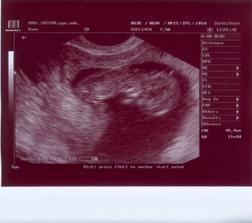

8.12.2009 ŠOK!!!!!!! Na testu //, ani nevíme, kde jsme k tomu mohli přijít 🙂